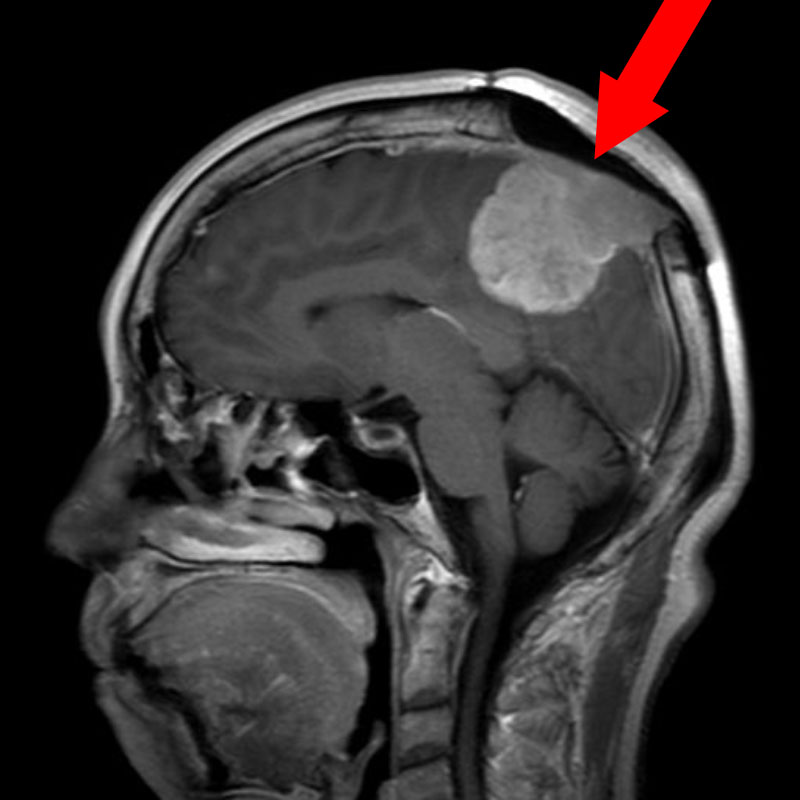

No.’25_22 手術前1

No.’25_22 手術前2